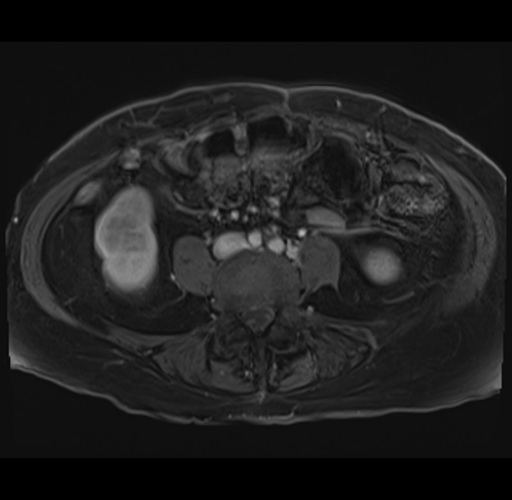

MRI T1

Imaging analysis